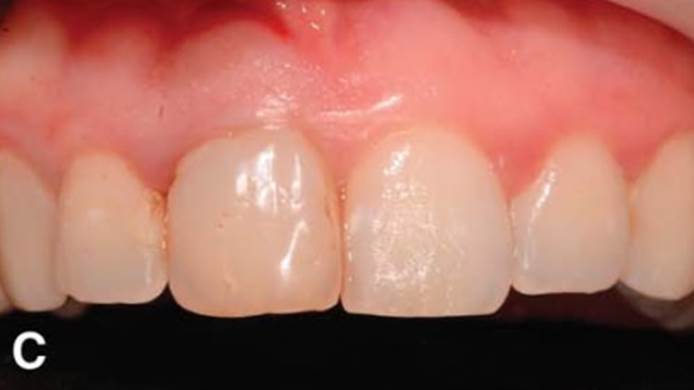

Clinical case: Replacement of fractured central incisor (#11) with immediate implant

& Root Membrane Technique

- Courtesy of Dr. Miltiadis Mitsias, Greece -

Keywords

AnyRidge, Root Membrane Technique, retrospective study, long-term study, immediate implants, bone resorption, bone preservation, Dr. Miltiadis Mitsias,survival, success, maxillary anterior, single replacement

Products:

AnyRidge implant system, Root Membrane kit

Reference

The Root Membrane Technique: A retrospective clinical study with up to 10 years of follow-up./Implant Dent. 2018 Oct;27(5):564-574

https://www.ncbi.nlm.nih.gov/pubmed/30161062